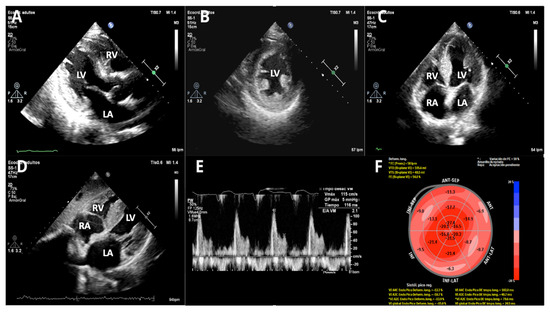

Background: The number of patients with transthyretin amyloid cardiomyopathy (ATTR-CM) has been increasing recently, and the early diagnosis and treatment of it are important. 99mTc pyrophosphate scintigraphy (99mTc-PYP) plays a key role in the early diagnosis of ATTR-CM. In patients [...] Read more.

Background: The number of patients with transthyretin amyloid cardiomyopathy (ATTR-CM) has been increasing recently, and the early diagnosis and treatment of it are important. 99mTc pyrophosphate scintigraphy (99mTc-PYP) plays a key role in the early diagnosis of ATTR-CM. In patients who underwent 99mTc-PYP, the early diagnosis of ATTR-CM by echocardiography was evaluated, focusing on left ventricular myocardial form and left ventricular wall thickness. Methods: The present study was conducted on 144 patients who underwent 99mTc-PYP between February 2020 and March 2024. A comparison was made between the 99mTc-PYP positive (P) and negative (N) groups, and significant factors were subjected to multivariate analysis. Results: 17 of 144 patients were positive (14.9%), and 15 patients were diagnosed with ATTR-CM by myocardial or skin (fat) biopsy. Other positive patients were also clinically considered to have ATTR-CM based on findings such as poor cardiac function and cerebral hemorrhage. 99mTc-PYP positive had a significantly larger CTR (60.3% in the P group vs. 53.9% in the N group, p = 0.007) and a larger left atrial diameter (42.8 mm in the P group vs. 40.0 mm in the N group, p = 0.047). On the other hand, the mean LV wall thickness was significantly thicker (15.7 mm in the P group vs. 12.8 mm in the N group, p < 0.001); however the LV end-diastolic diameter was smaller (41.9 mm in the P group vs. 48.4 mm in the P group, p < 0.001). The LV mass was similar in both groups, thus the relative left ventricular wall thickness (RWT), which indicates relative wall thickening, was significantly higher in the P group (0.85 in the P group vs. 0.52 mm in the N group, p < 0.001). The receiver operating characteristic curve of RWT for assessing 99mTc-PYP positivity had a cut-off value of 0.717 (area under the curve 0.862, 95%CI 0.763–0.961). Conclusions: The evaluation of wall thickness and RWT on echocardiography is important for diagnosing ATTR-CM. Full article